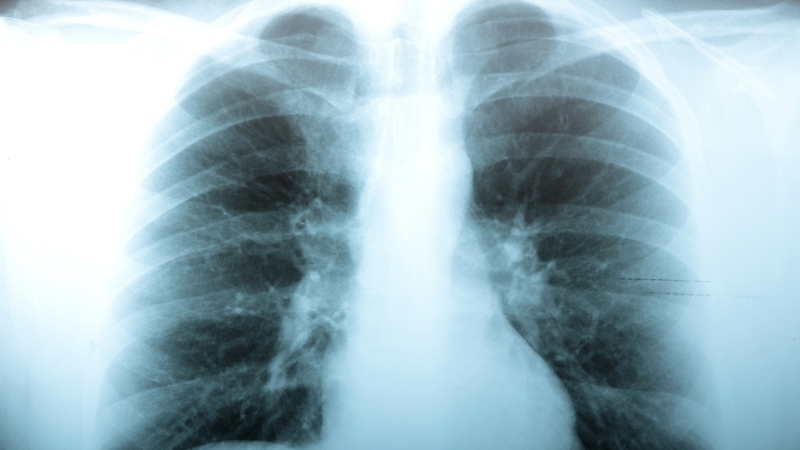

Scientists here have identified a significant mechanism that causes potentially deadly tuberculosis bacteria to disrupt the work of immune cells in the lungs.

They unearthed the method by which TB is able to block immune cells in the lungs of some patients during the early stages of infection, enabling it to establish itself.